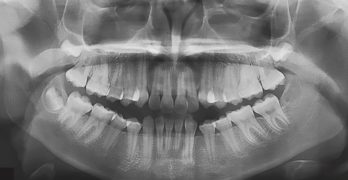

Tratamiento ortopédico de una maloclusión de clase III con mordida cruzada anterior profunda y discrepancia transversal

El artículo que compartimos el día de hoy con uds se llama Orthopedic Management of a Class III Malocclusion With Deep … [Leer más...] acerca de Tratamiento ortopédico de una maloclusión de clase III con mordida cruzada anterior profunda y discrepancia transversal